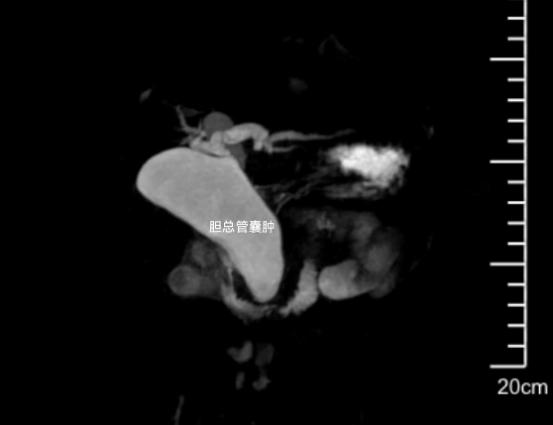

9月1日,我院水南院区儿科急诊来了一名年仅2岁的腹痛发热宝宝,其当地医院B超检查发现肝区有囊性回声,转来我院检查。入院后完善腹部影像学检查提示,小宝的肝总管及胆总管明显扩张(最宽处达3.1cm),诊断为先天性胆总管囊肿。该疾病属于先天性结构发育异常,是儿童常见的胆道畸形,若不及时干预,易引发胆汁淤积、胰腺炎甚至癌变风险,感染时症状加重,通过手术进行结构重建是根治这种疾病的最佳方案。